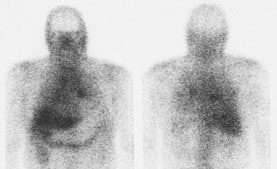

Sarcoid on Ga67 exam: The exam demonstrates diffuse pulmonary accumulation of the tracer consistent with active disease. Hilar acitivity appears asymmetric- but bilateral hilar activity can be seen (left more prominent on anterior image, right more prominent on the posterior image). SPECT imaging (not performed) would likely aid in assessment of mediastinal adenopathy. |